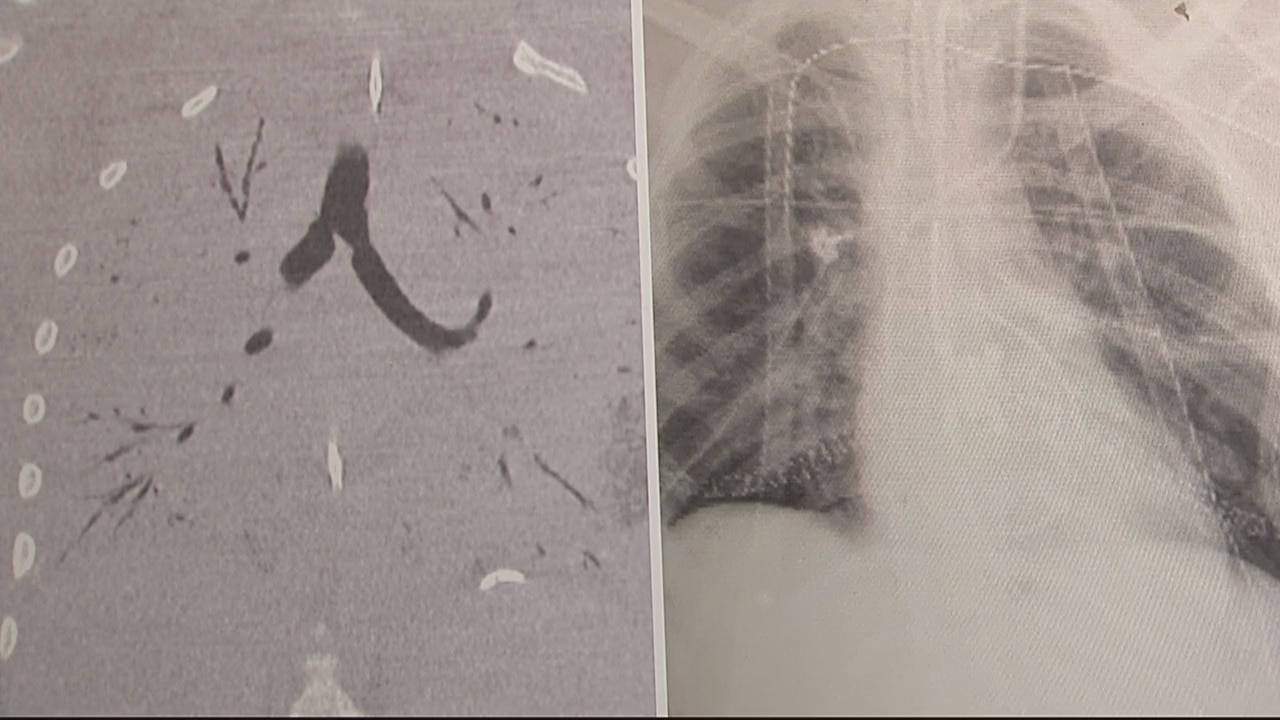

Henry Ford Doctor talks about the first double lung transplant realted to vaping

A 17 year old patient underwent a double lung transplant in October, after being hospitalized with injuries related to vaping. A doctor from the medical team joins us on The Nine to discuss the procedure.